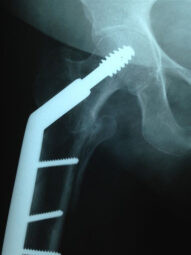

Fractura de Cadera